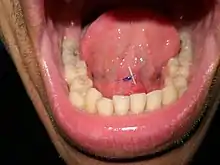

- Dents inférieures rétroclines (dents de la mandibule dirigées vers l’arrière et l’intérieur de la bouche) et plancher buccal profond (distance entre le haut des dents et la muqueuse de l’avant de la bouche sous la langue): ces caractéristiques anatomiques peuvent empêcher de placer le sialendoscope dans la bonne position de travail.

- Torus mandibulaires internes (formation osseuses bénignes de la face interne de la mandibule) qui peuvent empêcher l’introduction et les mouvements du sialendoscope.

Tous les gestes techniques sont effectués par voie orale. La papille (l’orifice naturel du canal salivaire dans la bouche) doit être dilatée avec des bougies en métal de diamètre croissant avant l’introduction du sialendoscope. Du sérum physiologique (envoyé par un canal laveur au sein du sialendoscope) est utilisé pour dilater et faciliter la progression du sialendoscope afin d’explorer les canaux salivaires. Parfois la papille est difficile à dilater et le chirurgien peut être amener à faire une petite incision dans le plancher de la bouche et ouvrir le canal en amont afin d’introduire le sialendoscope[16].